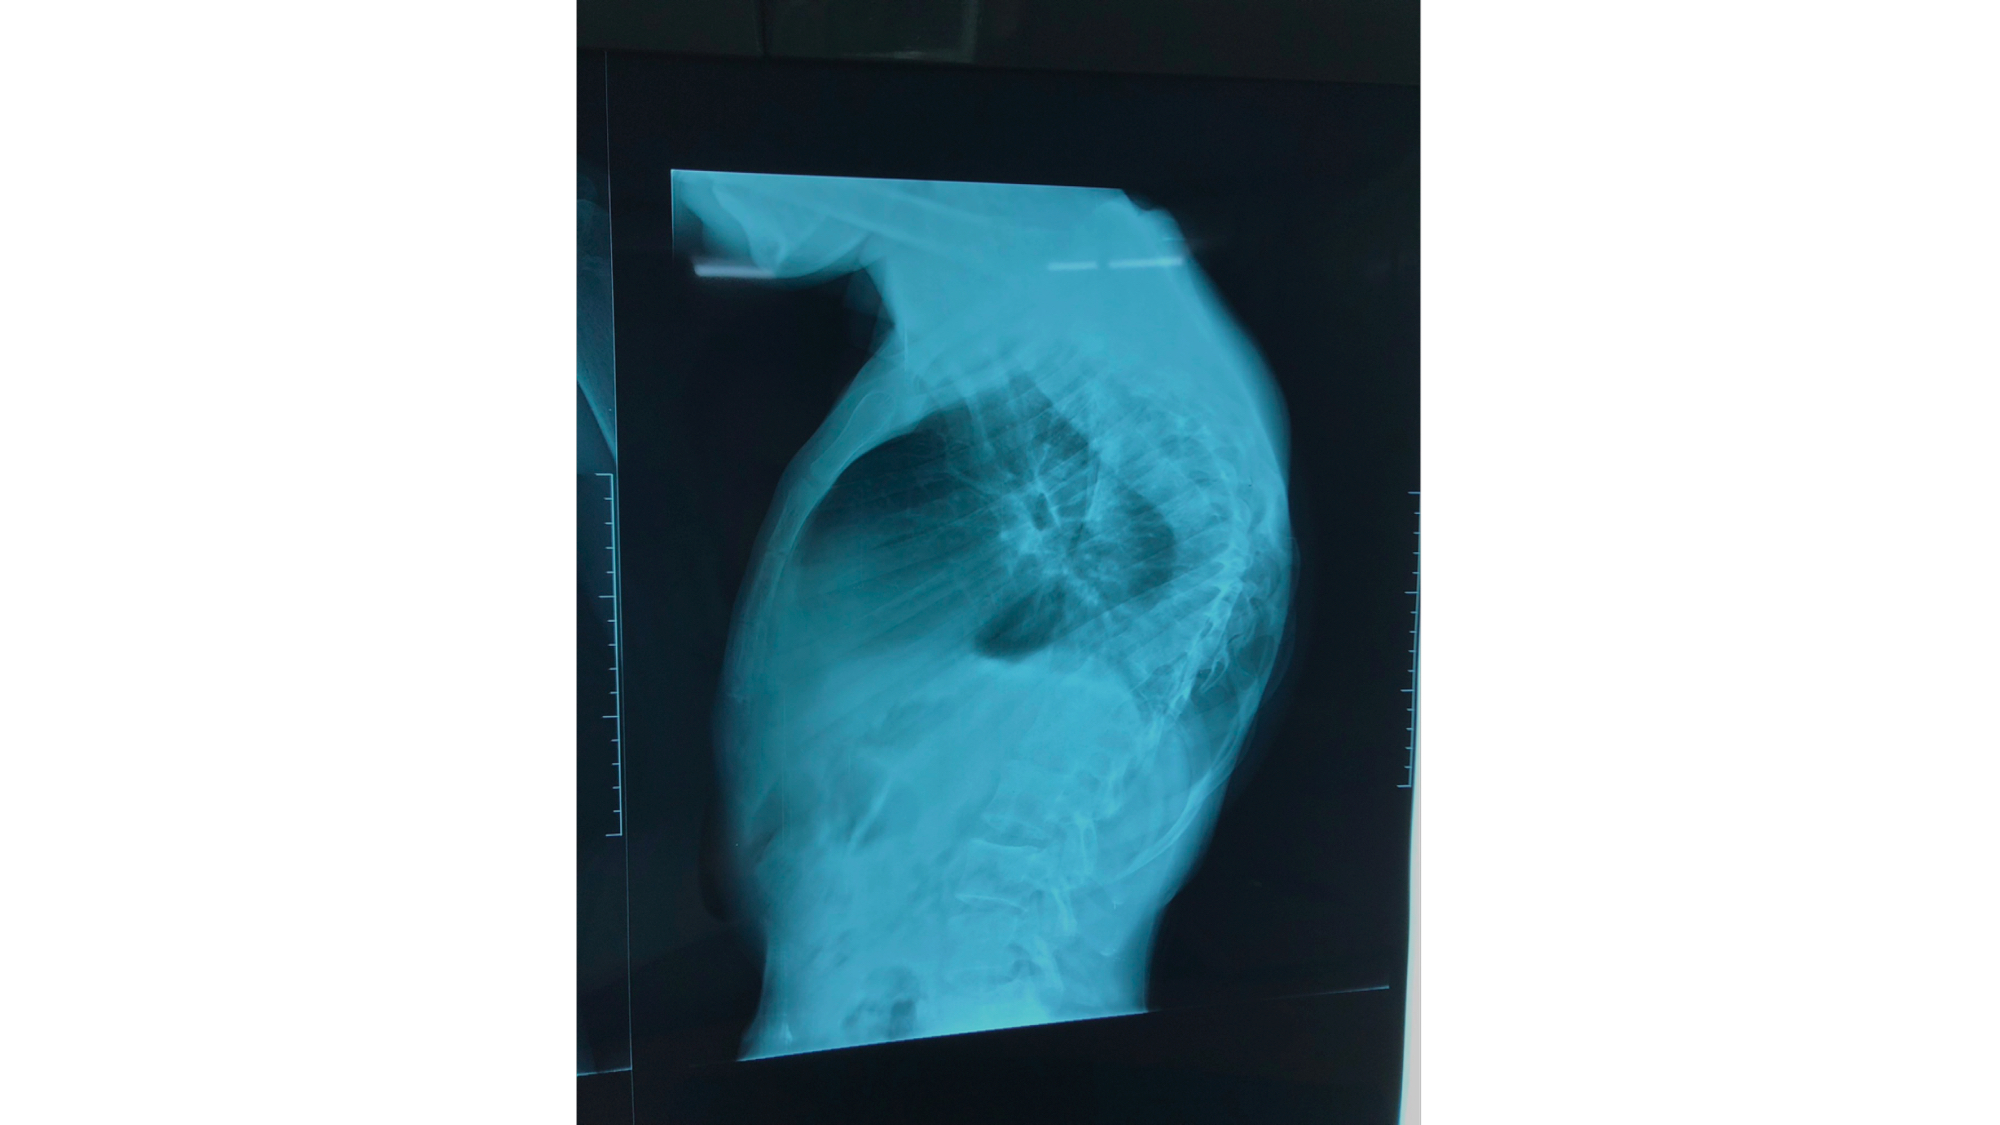

I was also able to meet the first two spine surgery fellows at AaBET. They are both neurosurgeons. The plan after next year is to alternate orthopedic with neurosurgery spine fellows. In addition to their teaching at AaBET, they are mentored by Dr Fasil Mesfin of Univeristy of Missouri, with whom they have weekly cases conferences. They were excited to show me two massive spine tumors they just operated on, one a giant, dumbbell shaped neurofibroma of the lower thoracic spine with bone involvement and preoperative paraparesis; the other a huge aneurysmal bone cyst of posterior lumbar element. Both needed pedicle screw instrumentation and big exposures. I am not a spine surgeon but the operative photos and postop xrays were very impressive.